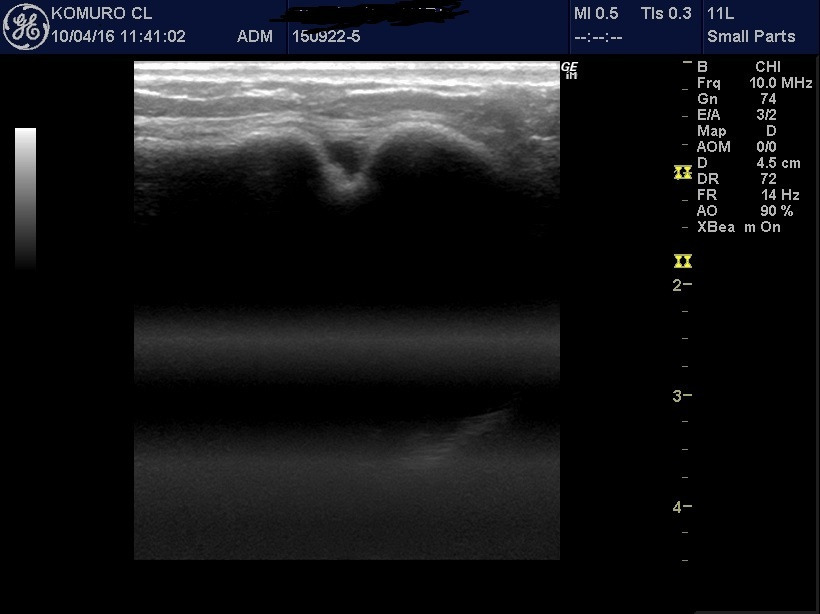

当院では、開院直後から超音波エコーを導入し、

バッグの破損の有無のチェックはもちろんのこと、乳がん検診も行っています。

そこで乳がんも含めて、胸に入っているバッグの状態を詳しく調べるのに役立つのが超音波エコーです。

マンモグラフィーと違い、バッグを傷つける心配がないので、問題なく検査を行うことが可能です。